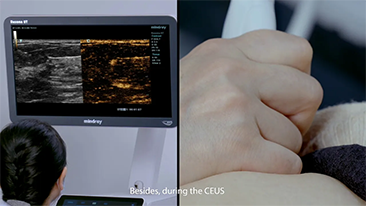

Mit den allgemeinen Bildgebungsl?sungen der Resona-Serie von Mindray k?nnen Arzt und ?rztin genauer und effizienter diagnostizieren sowie bessere Behandlungserfolge erzielen, durch umfassende geteilte Anwendung der Sonden und effiziente klinische Anwendungstools.

Das medizinische Umfeld ist komplexer geworden, die Zahl der schwierigen F?lle und Workloads gestiegen.